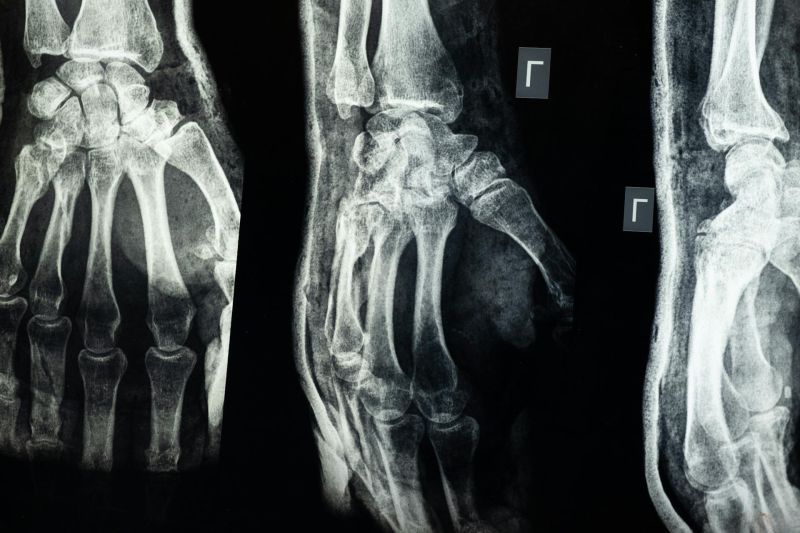

Multislajsni CT skener zglobova omogućava detaljan prikaz kostiju i mekih struktura koje učestvuju u pokretu. Na snimcima se jasno sagledavaju površine zgloba, okolni ligamenti i prostori između kostiju, pa se lekarima pruža pouzdan uvid u promene koje ne mogu da se uoče običnim rendgenskim snimkom.

Koje promene se mogu uočiti na snimcima

Pregledom se mogu otkriti oštećenja kostiju, promene u zglobnim površinama, nakupljanje tečnosti i prisustvo izraslina.

• Prelomi i nepravilnosti u položaju kostiju zgloba

• Degenerativne promene u zglobnim površinama

• Znaci zapaljenja i prisustvo tečnosti u zglobu

• Izrasline i nepravilnosti u strukturi tkiva

• Promene na okolnim mekim tkivima